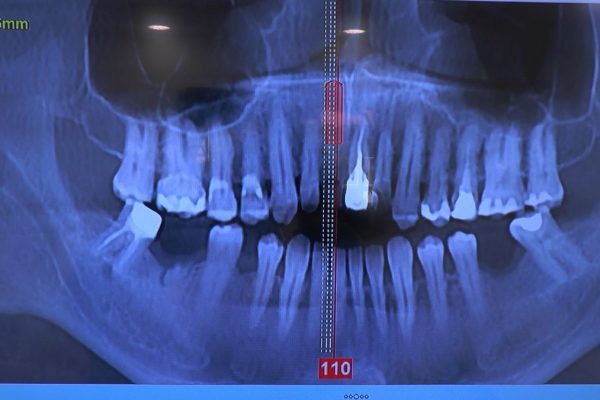

W ostatni weekend czerwca 2018 roku kursanci II Sezonu Preludium Implantologii odbyli piątą, finałową sesję, która w całości podporządkowana była praktyce. W ciągu dwóch dni zabiegowych Lekarze uczestniczący w szkoleniu przeprowadzili szereg zabiegów pod kierunkiem dr n.med. Violetty Szycik. Wszczepili 17 implantów oraz przeprowadzili ekstrakcje i zabiegi regeneracyjne kości. Zabiegi były wykonywane także w sedacji dożylnej z udziałem specjalisty anestezjologii i intensywnej terapii dr Jolanty Grzybowskiej. Preludium implantologii to nowy program edukacyjny dla adeptów implantologii stomatologicznej, którego celem jest wprowadzenie do implantologii poprzez pozyskanie wiedzy w szerokim zakresie i uwzględnieniem szczegółów mających decydujące znaczenie dla powodzenia leczenia implantologicznego. Ale tak jak wszystkie szkolenia w Instytucie Vivadental, w tym wiodące Practiculum Implantologii, zorientowane jest na praktyce i samodzielnym wykonywaniu zabiegów pod kierunkiem Mentora. To najlepsza edukacja w medycynie zabiegowej, a zarazem najlepszy start do implantologii.